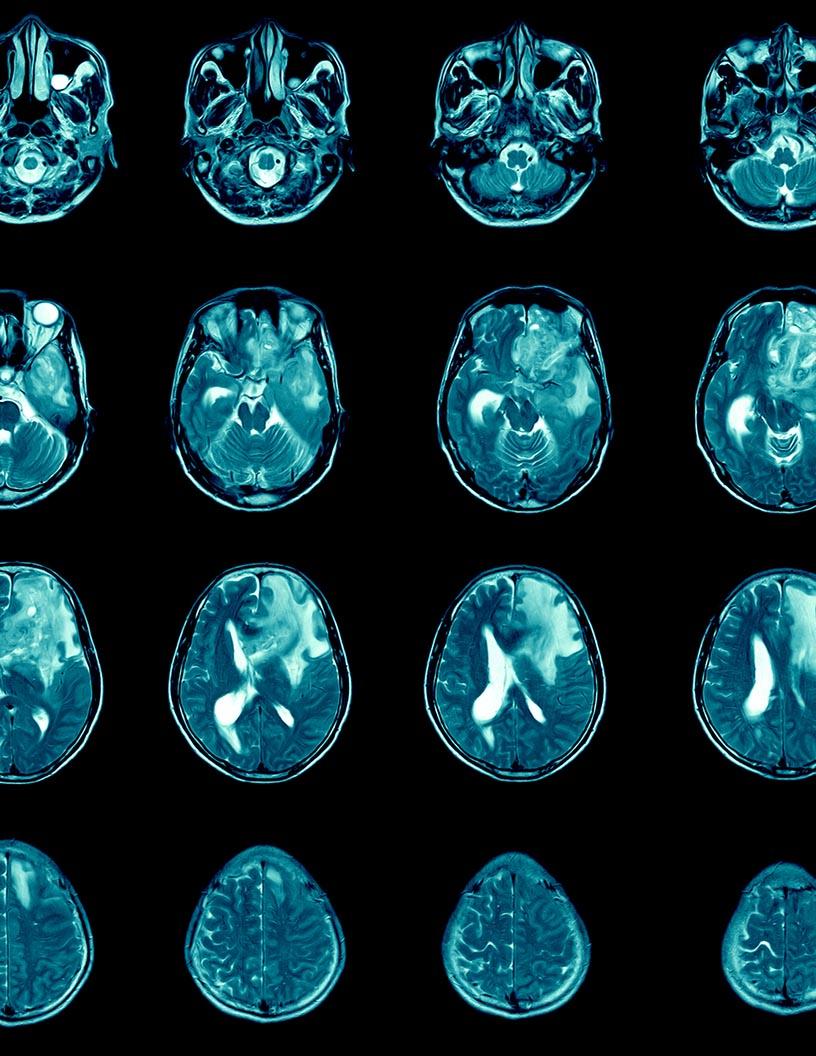

- The glioblastoma multiforme (GBM) treatment market is experiencing significant growth due to the rising incidence of this aggressive brain cancer and increasing research and development activities In the healthcare sector. According to the American Brain Tumor Association's Cancer Observatory, GBM accounts for approximately 15% of all primary brain tumors and is the most common malignant brain tumor in adults. Current treatment options include surgery, targeted therapy, and chemotherapy. Surgery remains the primary treatment modality for GBM, with various options such as awake craniotomy and awake craniotomy with intraoperative monitoring. This includes various strategies such as checkpoint inhibitors, monoclonal antibodies, and gene therapy. However, these procedures come with adverse effects such as cognitive impairment and motor deficits. Targeted therapies, such as temozolomide, are used in conjunction with surgery and chemotherapy to improve patient outcomes. The pharmaceutical supply chain plays a crucial role in ensuring the timely availability of these treatments to patients. Despite advancements in treatment options, the high mortality rate associated with GBM necessitates continued research and development efforts to improve patient outcomes and quality of life.

- Glioblastoma multiforme (GBM), a malignant tumor of the central nervous system (CNS), is a significant health concern worldwide. According to the Global Cancer Observatory, CNS cancers accounted for approximately 2.3% of all cancer diagnoses and 2.5% of cancer deaths in 2020. This article provides an overview of the current treatment landscape for GBM, focusing on surgical, radiation, chemotherapy, targeted therapy, immunotherapy, and emerging novel therapies. Surgery is the primary treatment modality for GBM, with the primary goal being to remove as much of the tumor as possible while minimizing damage to healthy brain tissue. Ambulatory surgical centers and hospitals offer various surgical procedures, including craniotomy and awake craniotomy. Following surgery, patients typically undergo radiation therapy to target any remaining cancer cells. External beam radiation therapy (EBRT) is the most common approach, delivering high-energy radiation to the tumor site. Chemotherapy is often used in combination with radiation therapy to enhance the therapeutic effect.